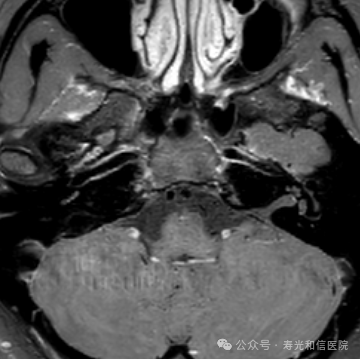

高场强设备(如3.0T MRI)提供更高分辨率的图像,能清晰显示血管狭窄、动脉瘤(≥3mm)、血管畸形等病变。研究显示,其对缺血性脑血管病的诊断灵敏度达95.2%,优于低剂量CTA。

一次检查可同时观察头颈部动脉主干及分支,结合平扫还能评估周围脑组织是否受损(如缺血灶),适合筛查脑卒中或复杂血管病变。